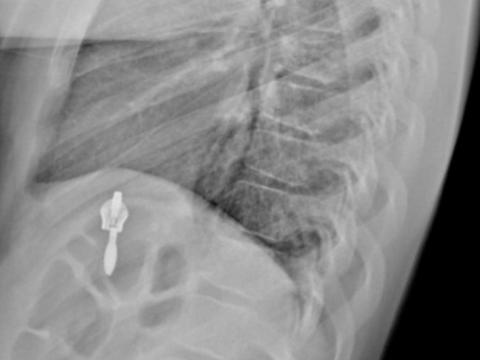

В травматологическое отделение Ивано-Матренинской детской больницы за сутки были доставлены пять детей с компрессионными переломами позвоночника. Четверо из них были госпитализированы, о чём сообщается в официальном телеграм-канале медицинского учреждения.

Один ребёнок получил травмы в результате падения на скользкой поверхности. Двое других пострадали во время прыжков на батутах в развлекательных центрах. Ещё один несовершеннолетний получил перелом на тренировке, а другой — во время спортивных соревнований.